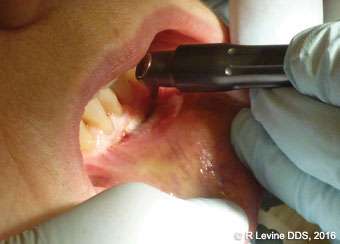

In comparison with conventional scalpel, the use of the CO2 laser in oral soft tissue surgeries offers several benefits. Among these benefits are cutting in a non-contact mode (which helps to avoid mechanical trauma to the tissue) and without bleeding or the need for sutures, precise tissue removal, and minimized postoperative pain, edema, and inflammation. The use of a CO2 laser on the oral soft tissue has no known contraindications or side effects.[5] A substantial body of peerreviewed literature describes the excellent hemostatic capacity of the CO2 laser as a useful instrument for oral surgery in patients with hemorrhagic disorders or undergoing antithrombotic therapy (Figures 3A-3B).[5-8] Due to the hemostatic ability of the CO2 laser, intraoral surgical wounds often can be left to heal by secondary intention without placing sutures or dressing (as in Cases 3, 5, 7, and 8 described in this article).[10] For example, the patient in Case 1 (Figures 3A-3C) wanted to have a vascular lesion (capillary hemangioma on the lip) removed. The risk of intraoperative hemorrhage was elevated by the fact that the patient had been taking blood thinning agents for his atrial fibrillation condition. In addition, the lesion was located in the area where successful cosmetic outcome was important; therefore, it was crucial to have good visualization of the operatory field. Efficient intra-operative hemostasis provided by the CO2 laser allows for more precise and accurate tissue removal due to the improved visibility of the surgical field (Figure 3B).[9] In this case, the CO2 laser enabled the clinician to achieve the best results in a short period of time. No sutures were placed, and a thin layer of char was created to protect the surgical site. The recovery was uneventful. Figure 3C shows the completely healed surgical site at 1 month postoperatively.

Figures 4A-4B, 5A-5B, 6A-6C, 7B-7C, and 8A demonstrate the enhanced hemostasis ensured by the LightScalpel CO2 laser. In Case 2, the patient had the vestibular extension procedure performed, and the hemorrhage was very well controlled, enabling the clinician with utmost precision. In Case 3, the bloodless excisional biopsy of fibroma was performed. Case 4 is a stage II implant uncovering procedure. This surgery requires both special accuracy and the well-controlled depth of laser energy penetration as well as enhanced hemostasis. No blood was present at any point. The implant was uncovered in approximately 30 seconds. In connection with implant uncovering, it should be mentioned that the recent study on the 10,600 nm CO2 laser removal of biofilm from titanium implant surfaces[11] reported that this laser wavelength does not affect titanium or titanium oxide (most common implant materials) and is therefore safe to use around implants. Case 5 shows a LightScalpel CO2 laser lingual frenectomy in a 7-year-old patient. Surgery is performed in a highly vascularized area where bleeding was well controlled. Finally, Case 6 is the ablation of the inflamed operculum. Figure 8A demonstrates the immediately postoperative view with excellent hemostasis.